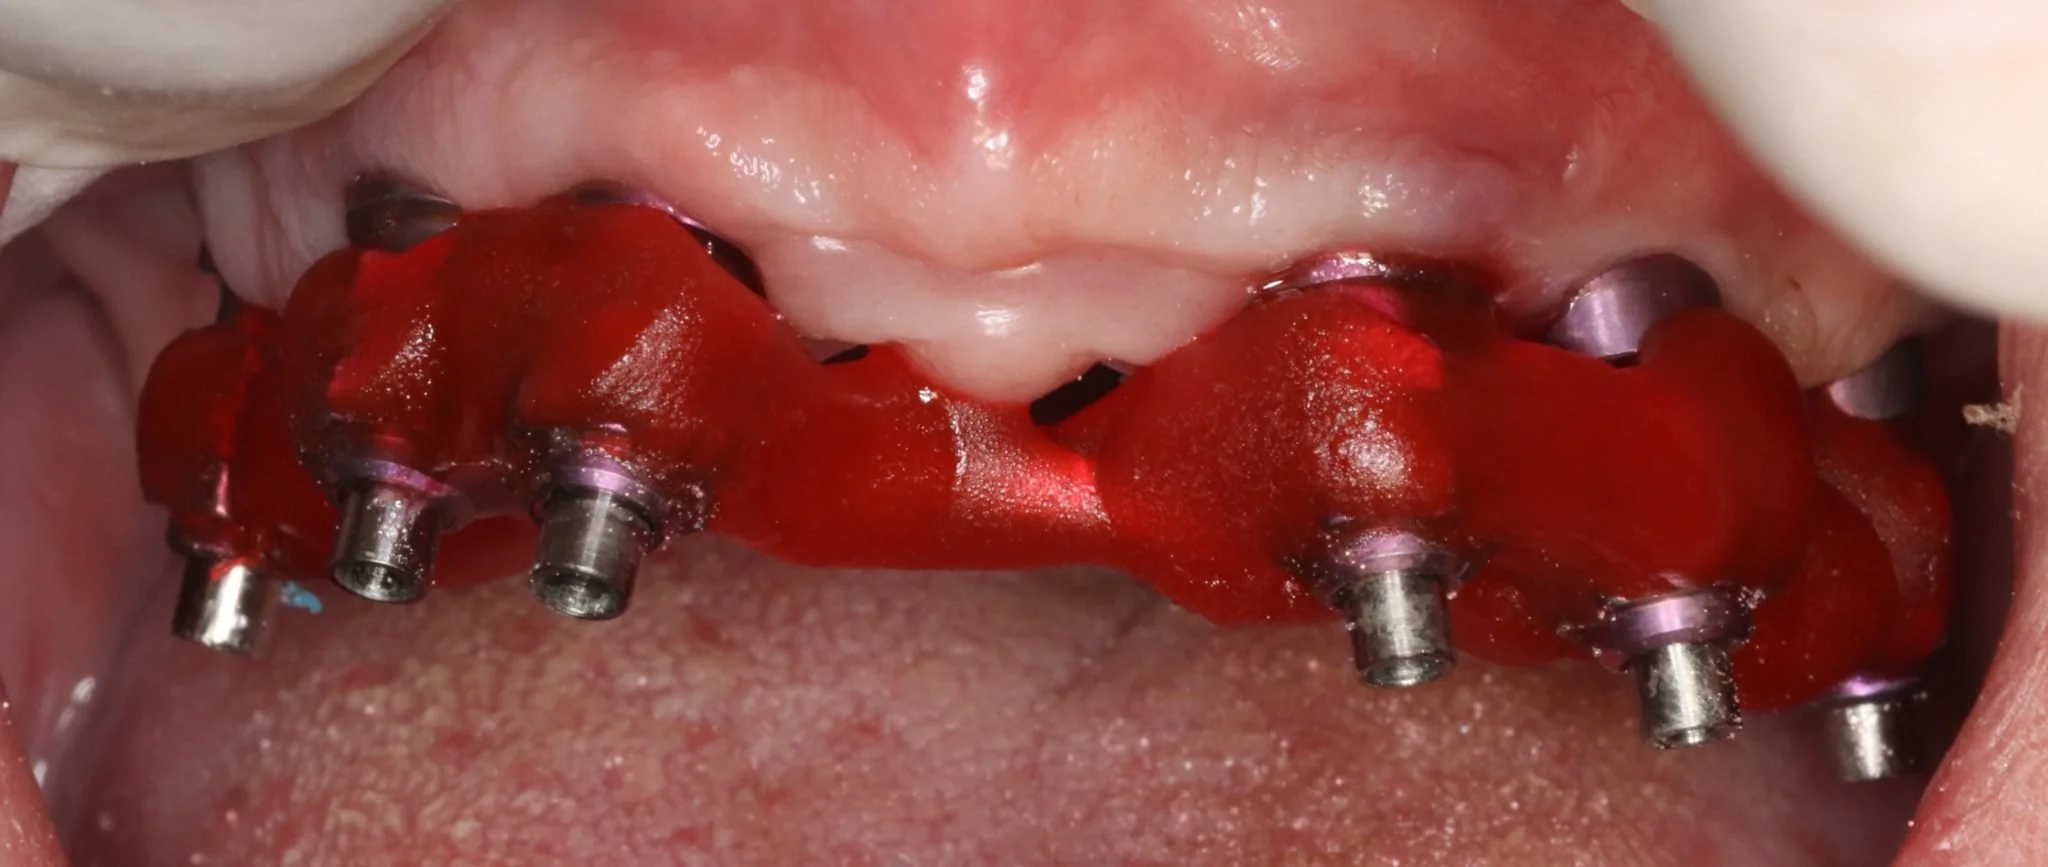

Multiple intra-operative radiographs were taken using depth gauges of gradually increasing diameter to ensure ideal positioning, particularly near vital structures such as the maxillary sinus. Following three months healing, definitive impressions were taken. Radiographs were taken to confirm complete seating of the impression copings prior to splinting of the impression copings and then impression taking.

Impression copings were splinted together using metal wire and gradual incremental buildup with Fuji Pattern resin (GC Corp). Care was taken to avoid buildup of stresses in the resin leading to distortion in the impression. Addition-cured PVS impression material (Take One, Kerr) was allowed to complete the set before removal. Silicon-based trays are often used so that the guide pins are easily accessible prior to removal. impressions were poured and master cast were constructed in the laboratory

Records stage: due to the fact that all records were gained by the adjustment and confirmation of the provisional removable complete maxillary denture, records were quite straightforward. The complete denture was copied, flanges were removed, and the resulting guide was then seated over the existing tissue level healing abutments. A PMMA bridge with plastic inserts was constructed digitally in the laboratory and sent for final confirmation prior to construction of the definitive porcelain-fused-to-zirconia bridge. The definitive bridge was inserted and radiographs were taken to confirm full seating and correct emergence profile. Once passivity of fit was confirmed, abutments crews were torque to 35 Ncm, and the access cavities were restored with PTFe tape and composite resin. The occlusion was adjusted to ensure guiding services were smooth, concave and gradually increasing pre-truce in steepness, and smooth shared group function in lateral excursion.